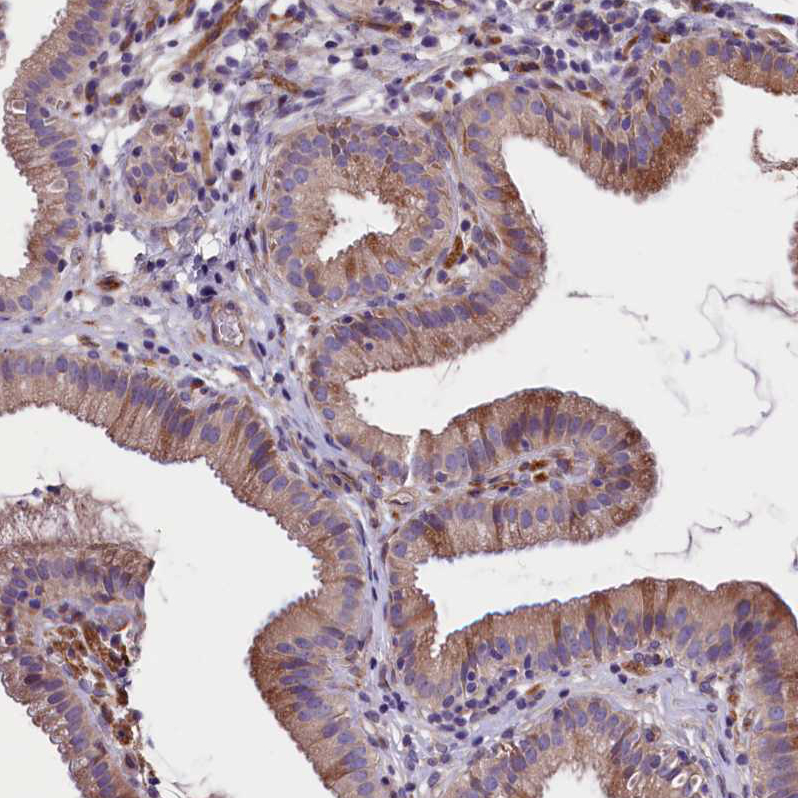

Immunohistochemical staining of human gallbladder shows strong cytopalsmic and membranous positvity in glandular cells.